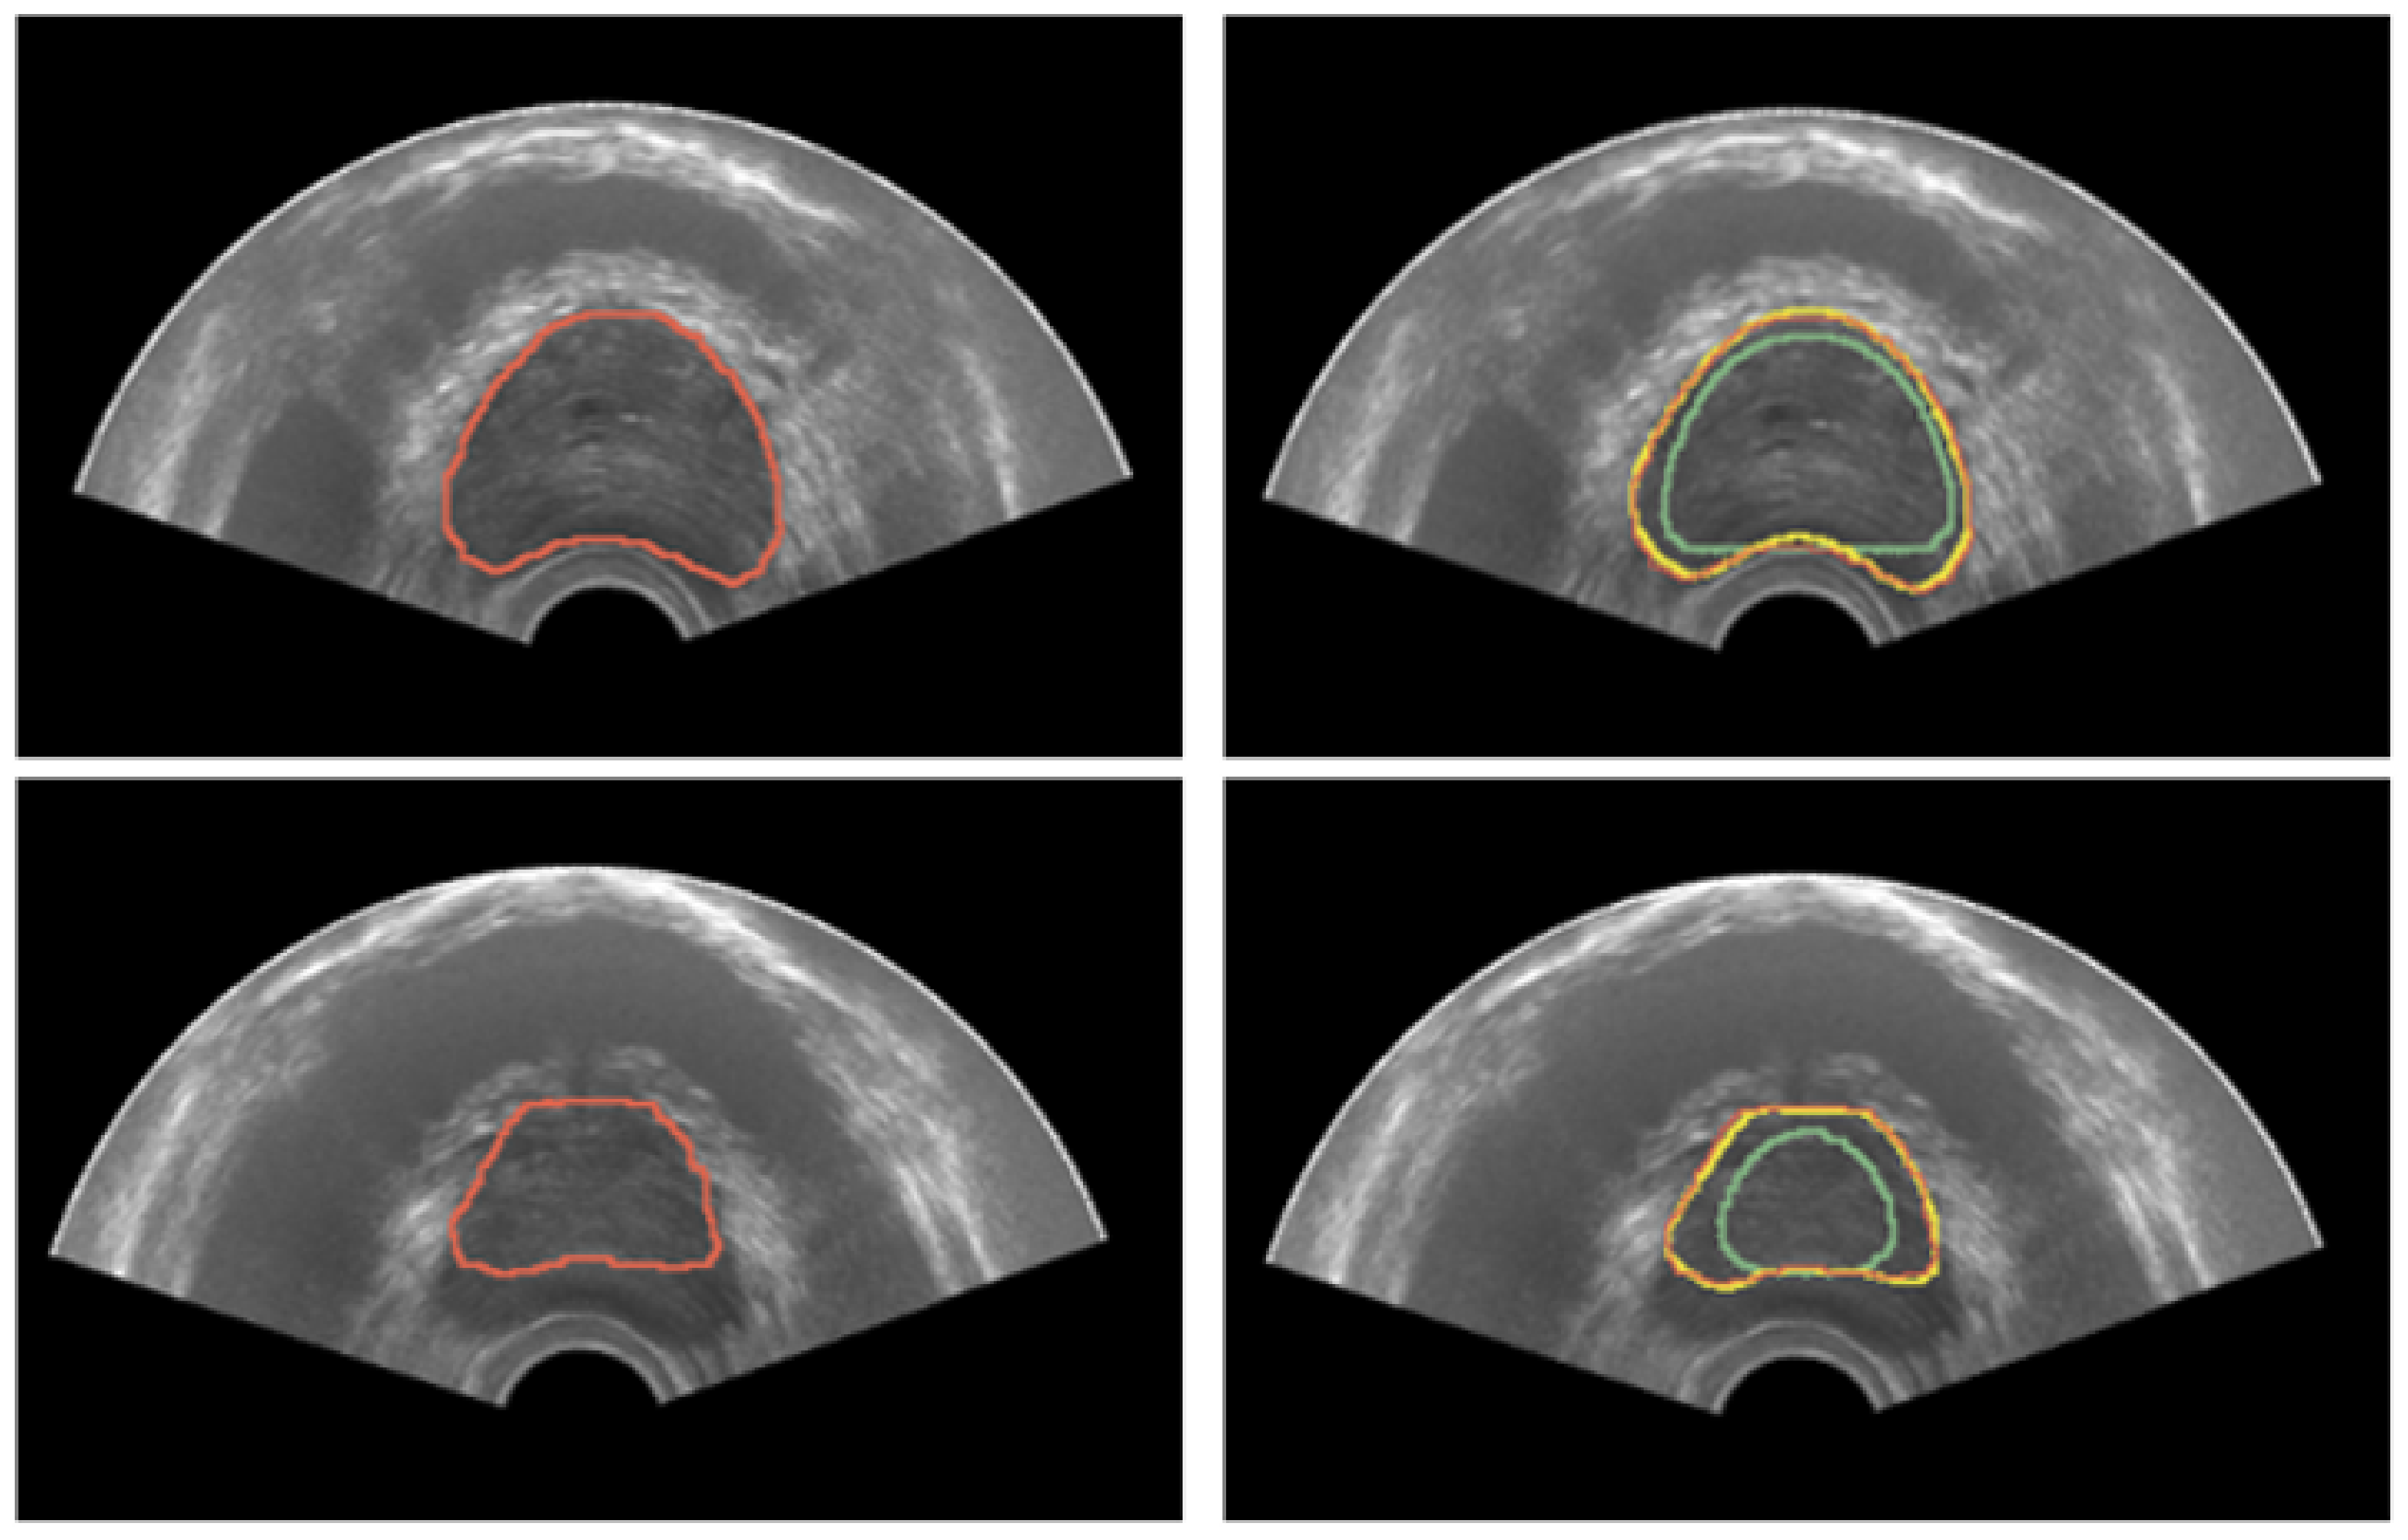

Quantitative results for TRUS segmentation with the developed methodology based on deformable superellipses are reported in Table 3, whereas sample segmentation images are depicted in Figure 9. Three experiments have been conducted per each case, placing 4 points on the base and 4 on the apex, using only the superellipse to fit the contours. Instead, on the mid-gland, a number of points varying from 10 to 12 has been considered, exploiting B-splines before fitting the superellipse to finally achieve the 3D modeling of the prostate gland. Results are reported as mean ± std of the experiments performed on each case. It is possible to see that results are considerable overall, with the Dice coefficient being greater than 87% in all cases. Moreover, the proposed implementation is iterative, so that the user can refine the results until it reaches the desired performance. For the purposes of this research, the experiments stopped at second iteration, which allowed the results to be improved in all cases.

Figure 9.

Results for prostate segmentation from TRUS. The left image portrays the ground-truth prostate mask in red. The right image depicts the segmentation results after both the first and second iteration in green and yellow colors, respectively.